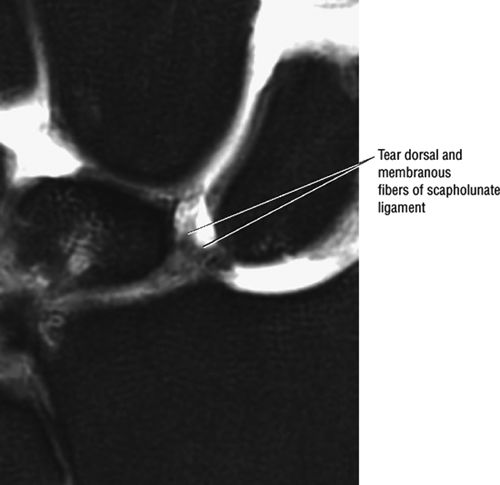

Disruption of the scapholunate ligament is shown on T2*-weighted or STIR images as either complete ligamentous disruption or as a discrete area of linear hyperintensity in a partial or complete tear (Fig. 10.90).

Axial MR images are used to distinguish among tears of the dorsal, membranous, and volar portions of the scapholunate ligament. The location of the tear can then be directly correlated with dorsal or volar coronal images.

Potential sites of injury of the intrinsic scapholunate ligament complex (the scapholunate interosseous ligament) (Fig. 10.92) include its dorsal component (an important key stabilizer), a membranous component, and a volar component.

Dissociation (Fig. 10.96), indicated by an increased scapholunate gap (more than 3 mm), comparable to the Terry Thomas sign on radiography

DISI with dorsal tilting of lunate, an increased capito-lunate angle (more than 30°), and an increased scapho-lunate angle (more than 80°) (Fig. 10.98)

Disruption of the dorsal component of the scapholunate ligament